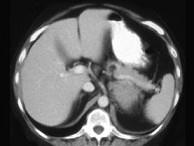

问题 女,47岁,满月脸、向心性肥胖伴高血压1个月,请结合所提供图像,作出诊断()

选项 A.左肾上腺腺瘤 B.左肾上腺腺癌 C.左肾上腺转移瘤 D.左肾上腺嗜铬细胞瘤 E.左肾上腺增生

答案 B